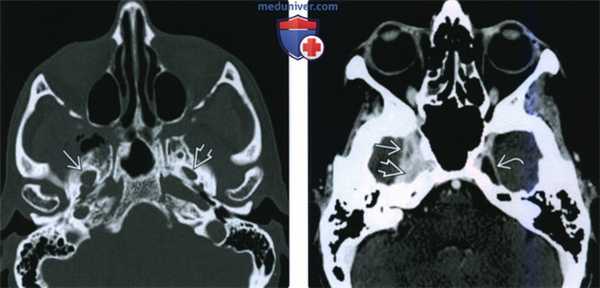

(Слева) КТ в костном окне, аксиальная проекция. По сравнению с нормальным левым овальным отверстием правое овальное отверстие увеличено в размерах. Расширение отверстия обусловлено распространением злокачественной опухоли по нижнечелюстному нерву.

(Справа) КТ с КУ, аксиальная проекция. По волокнам нижнечелюаного нерва опухоль распространилась в тройничную полость и среднюю черепную ямку. Обратите внимание, что с левой стороны тройничная полость имеет нормальную плотность, соответствующую плотности спинномозговой жидкости.